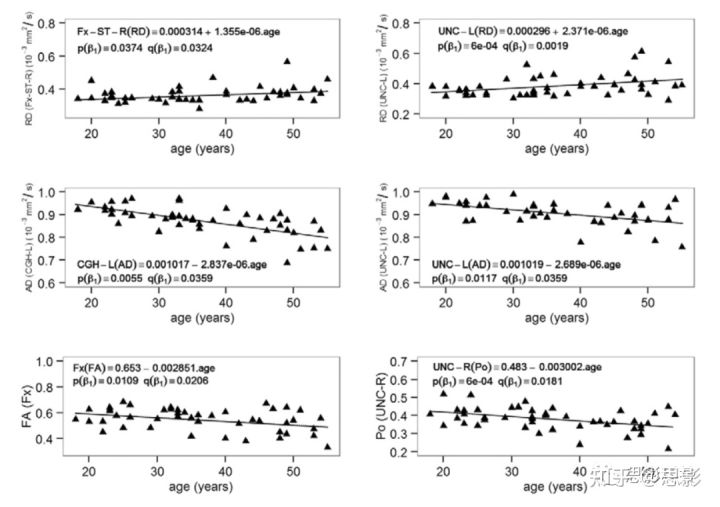

因为在回归模型1中,所有的扩散指标和ROI组合下β3都不显著,因此老化效应在两性中是一致的。因此,无论是回归模型2还是回归模型3的β1都被用来描述男女共同的老化效应。表3总结了白质ROI中那些显著的β1(斜率),图4显示了这些斜率每十年的变化百分比。图5为年龄相关的重要ROI中DTI和q空间分析的显著回归曲线。ODI的回归线如图6。DTI扩散指标随年龄变化的总体趋势是AD降低,RD增加,FA降低。MD在年龄上没有显著差异。同样,组织限制(P0)在大多数白质ROI中相对稳定,但在2个ROI中(包括钩状束,UNC)显著下降。与年龄相关的NODDI指标变化的总趋势是增加了纤维弥散度(ODI),其中显著的白质ROI发生率最高。轴突内体积分数(ICVF)稳定,所有白质ROI无显著变化。

图5 模型3的DTI(RD、AD和FA)和q空间(P0)指标在年龄相关的关键ROI中的显著线性回归结果,包括穹窿(Fx)、穹窿终纹(Fx-ST)、钩状束(UNC)和海马扣带回(CGH)。老化率β1如表3。P值表示未校正的显著性水平,q值表示48个ROI的多重比较的错误发现率(FDR)。Q<0.05 被认为是显著的。

图6 模型3中NODDI-ODI在年龄相关的关键ROIs中包括穹窿终纹(Fx-ST)和海马扣带回(CGH)的显著线性回归结果。

老化速率β1如表3。p值表示未校正的显著性水平,q值表示48个ROI的多重比较的错误发现率(false discovery rate,FDR)。Q<0.05被认为是显著的。

扩散指标之间的关系

如表3和表S2所示,19%的FA-显著降低的ROI的AD也显著降低,76%的FA-显著升高的ROI的RD显著升高,AD降低或RD升高的情况下FA-显著变化的ROI为86%,所有FA-显著ROI的ODI均升高。所有AD和RD显著变化的ROI也随着年龄的增长而发生显著的ODI变化,只有一个RD显著的ROI。FA、AD和RD与ICVF或P0无关。